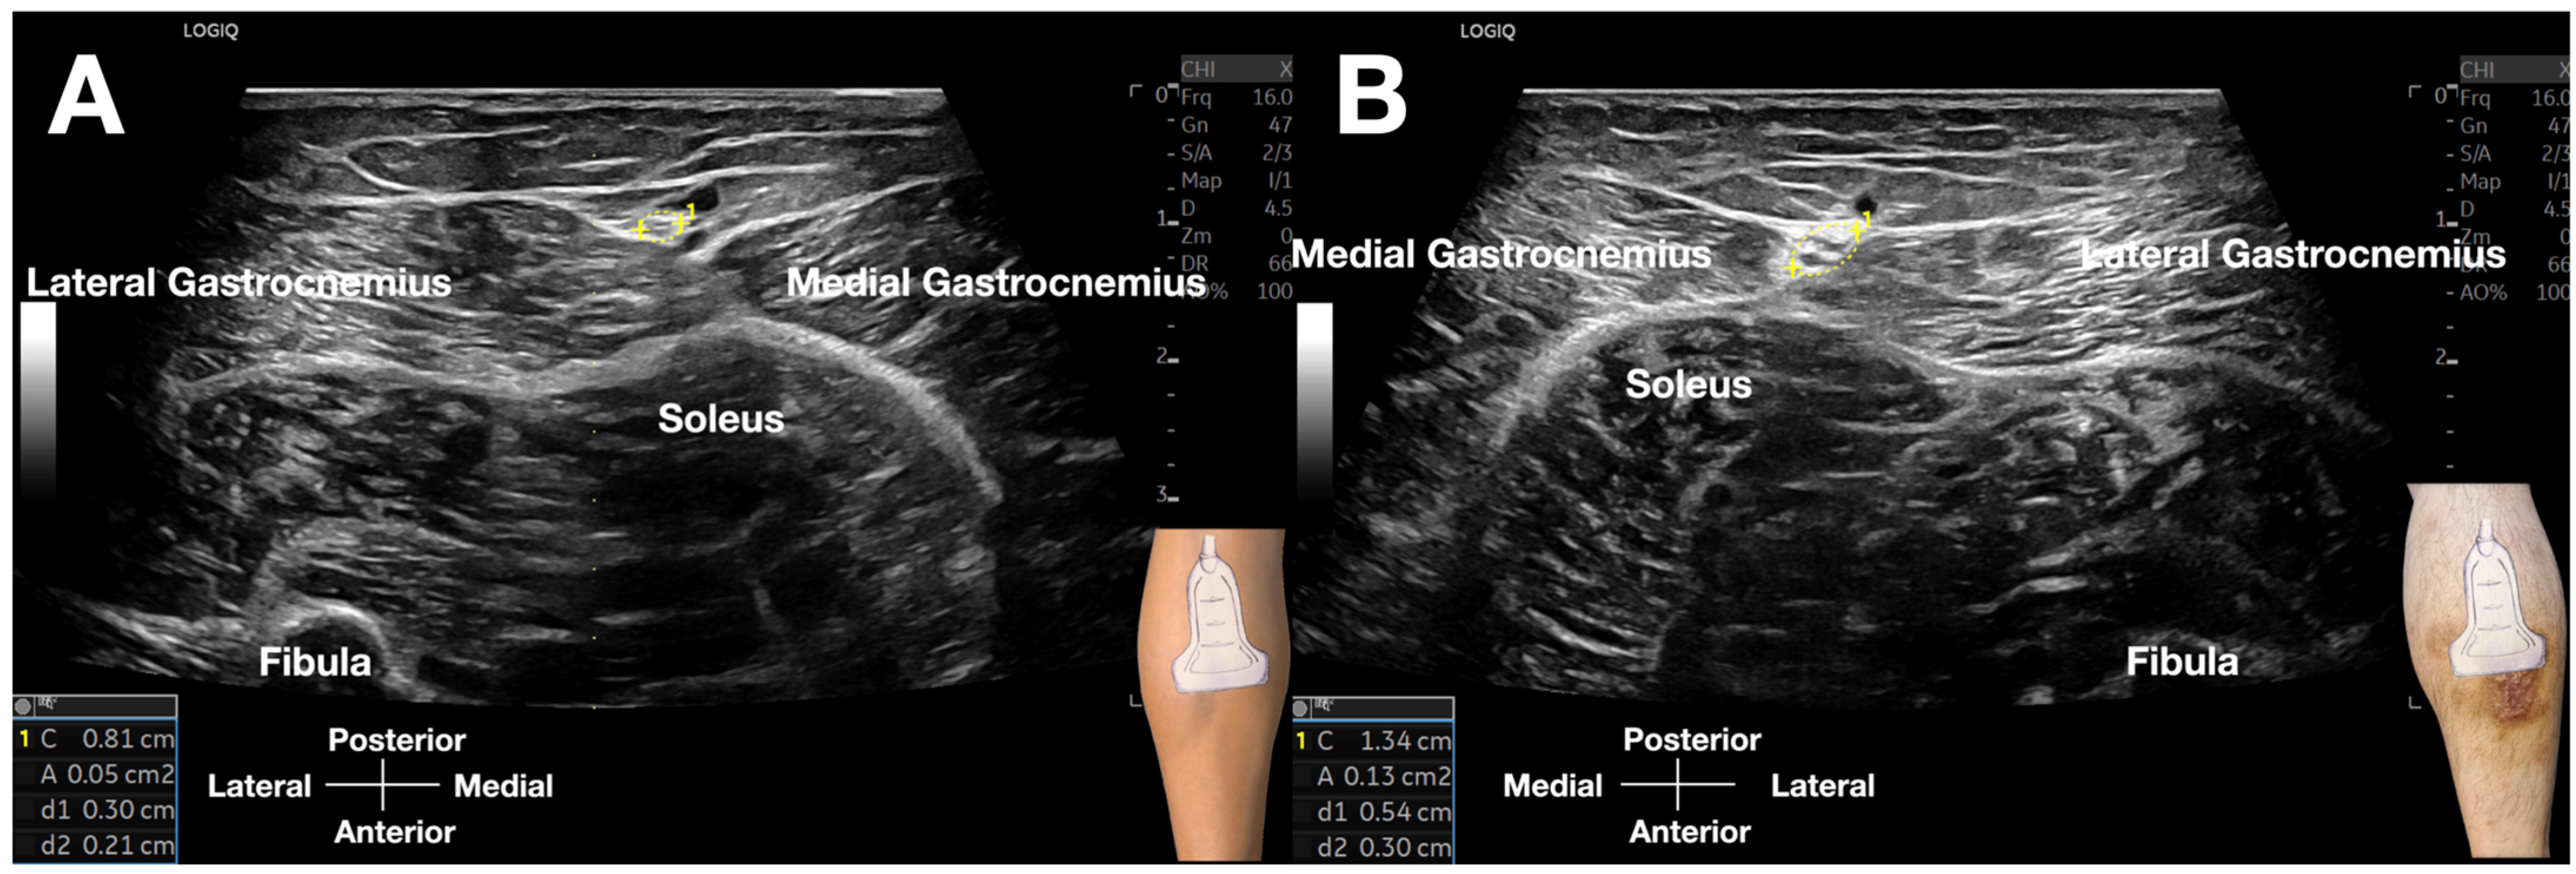

Sonoguided Digital Palpation (SDP) represents a dynamic diagnostic technique integrating real-time ultrasonography with targeted layer palpation [3], grounded in established osteopathic principles of myofascial and visceral assessment [32,33,34,35,36,37,38]. This methodology enables direct visualization and quantification of tissue tension abnormalities and interfacial friction dynamics. In the present case, SDP was employed to evaluate the crural fascia (CF), wherein restricted gliding mobility relative to superficial adipose tissue or underlying gastrocnemius musculature signified fascial pathology (Figure 4 and Video S1). A critical advantage of this approach is the capacity for real-time contralateral comparison, providing an internal control for biomechanical assessment.

Figure 4.

Comparative cross-sectional ultrasound images of the sural nerve (SN). (A) Asymptomatic left leg: The SN (calipers) within the crural fascia’s fatty triangle demonstrates a normal cross-sectional area of 5 mm2, with preserved fascicular architecture and no perineural edema. (B) Symptomatic right leg: The SN (calipers) is significantly enlarged, with a cross-sectional area of 13 mm2, loss of fascicular definition, and surrounding hypoechoic edema, consistent with nerve pathology and fascial restriction.

The technique was executed with controlled digital pressure (estimated 2–4 kg/cm2) applied rhythmically for 10–15 s intervals at each assessment site, utilizing alternating lateral-to-medial and medial-to-lateral vectors (Figure 3, Video S1). Diagnostic interpretation followed a validated four-criterion protocol [3]: (1) Quantitative fascial mobility restriction (≤5 mm transverse excursion versus >5 mm contralaterally); (2) Precise reproduction of concordant Achilles pain upon sural nerve (SN) provocation; (3) Identification of crural fascial gliding impairment; (4) Sonographic evidence of significant nerve swelling, with a cross-sectional area (CSA) of 13 mm2 on the affected side, compared to 5 mm2 on the contralateral, asymptomatic side (Figure 4, Video S2), alongside perineural edema and fibrotic tissue changes.

Selective application of SDP within the crural fascia’s fatty triangle—an anatomical space bounded by the medial and lateral gastrocnemius muscles—facilitated assessment of sural nerve (SN) and lesser saphenous vein (LSV) mobility relative to adjacent structures. Diagnostic criteria for symptomatic SN involvement included: reproduction of characteristic Achilles pain upon neural palpation, palpable tethering with restricted nerve mobility, and increased gliding resistance. Additionally, layered palpation excluded myofascial trigger points in the gastrocnemius and soleus muscles through depth-specific pressure application; the absence of twitch responses further differentiated neuropathic from myogenic pain etiologies.